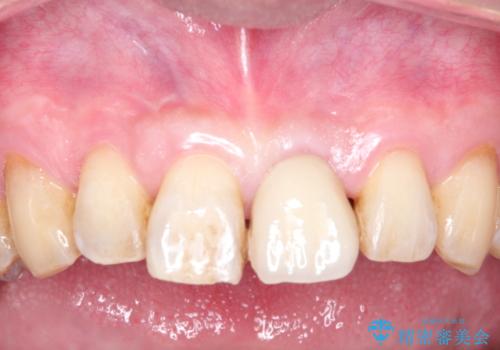

歯についている茶しぶやタバコによるヤニは着色を落とす専用器具を使用しないと綺麗に取り除くことはできません。

歯の表面に着色が付いて黄ばんで見えることがあるため、PMTCを行うとご自身の歯本来の色味にすることができます。

エアフローはお水と強圧の風と細かいパウダーでお掃除していきます。

そのため、ブラシでは届きにくかった歯と歯の間の汚れをより落とすことが可能になります。